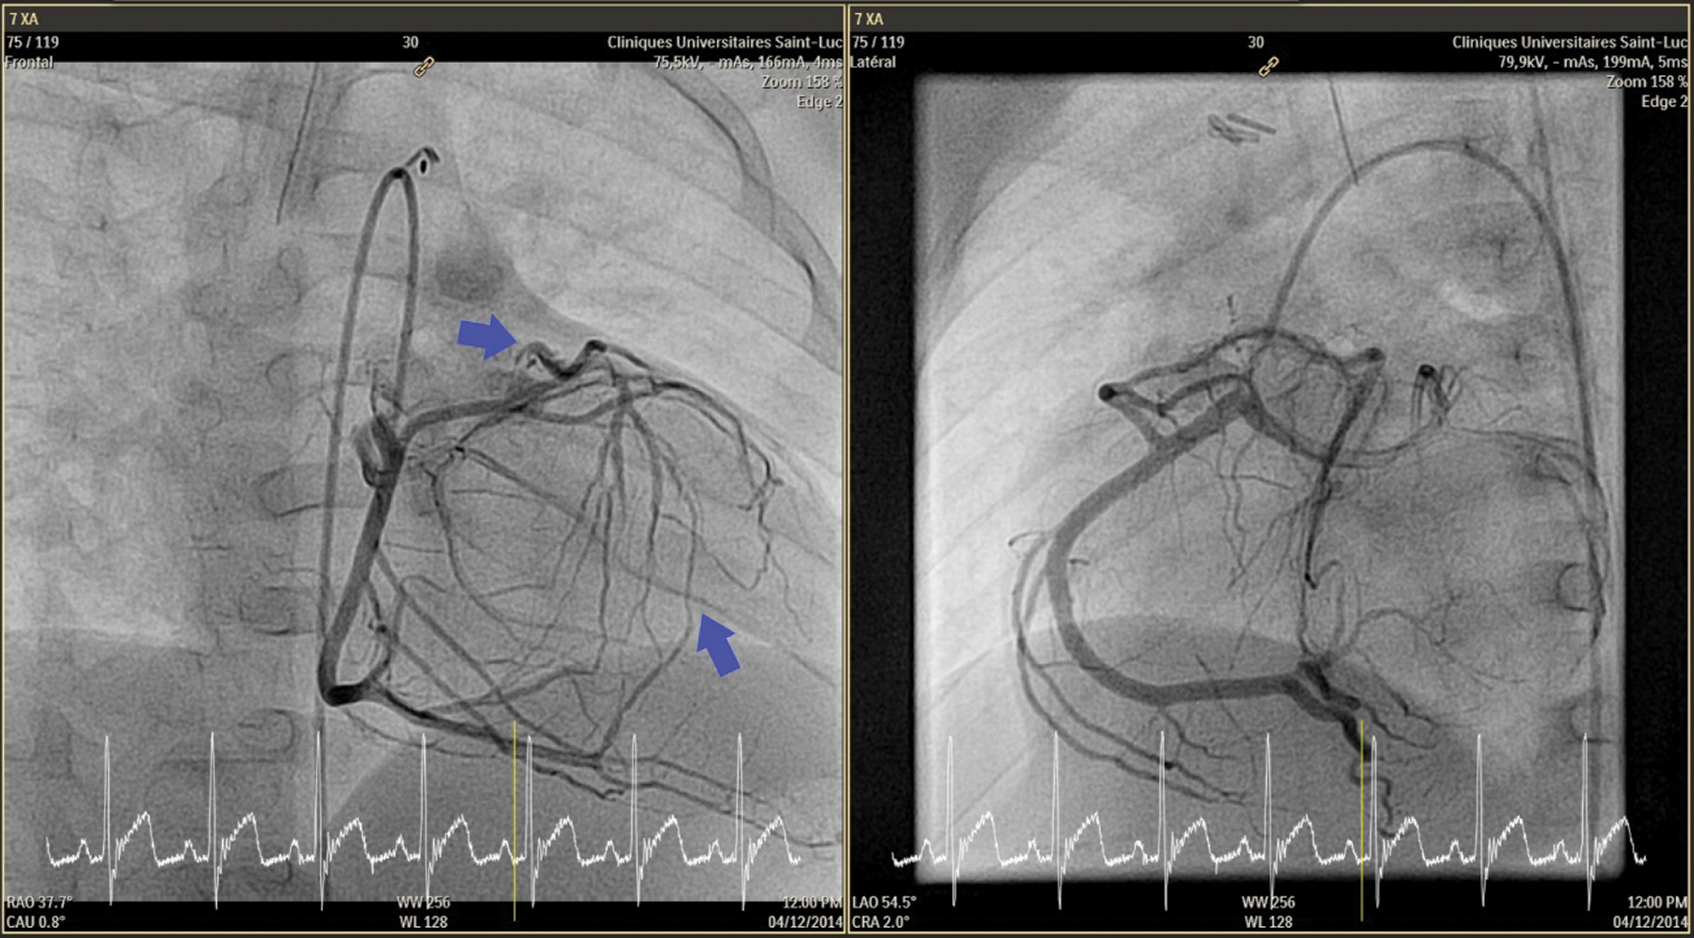

The patient was asymptomatic. The physical examination at admission showed a systolic murmur 3/6 maximum at the pulmonary focus and radiating into the back and no signs of heart failure was present. The electrocardiogram was normal, and the echocardiographic study showed a mild septal dyskinesia. The cardiac catheterization and the angio-CT demonstrated a rare coronary pattern: 1- proximal LAD and 2-RCA-Cx-distal LAD pattern (posterior loop) and severe proximal stenosis of “LAD” arising from pulmonary artery (Figs. 1–4).

Figure 1: Cardiac catherization: RCA gives Cx. Reverse flow from multiples collaterals in the small LAD which originates from the pulmonary artery